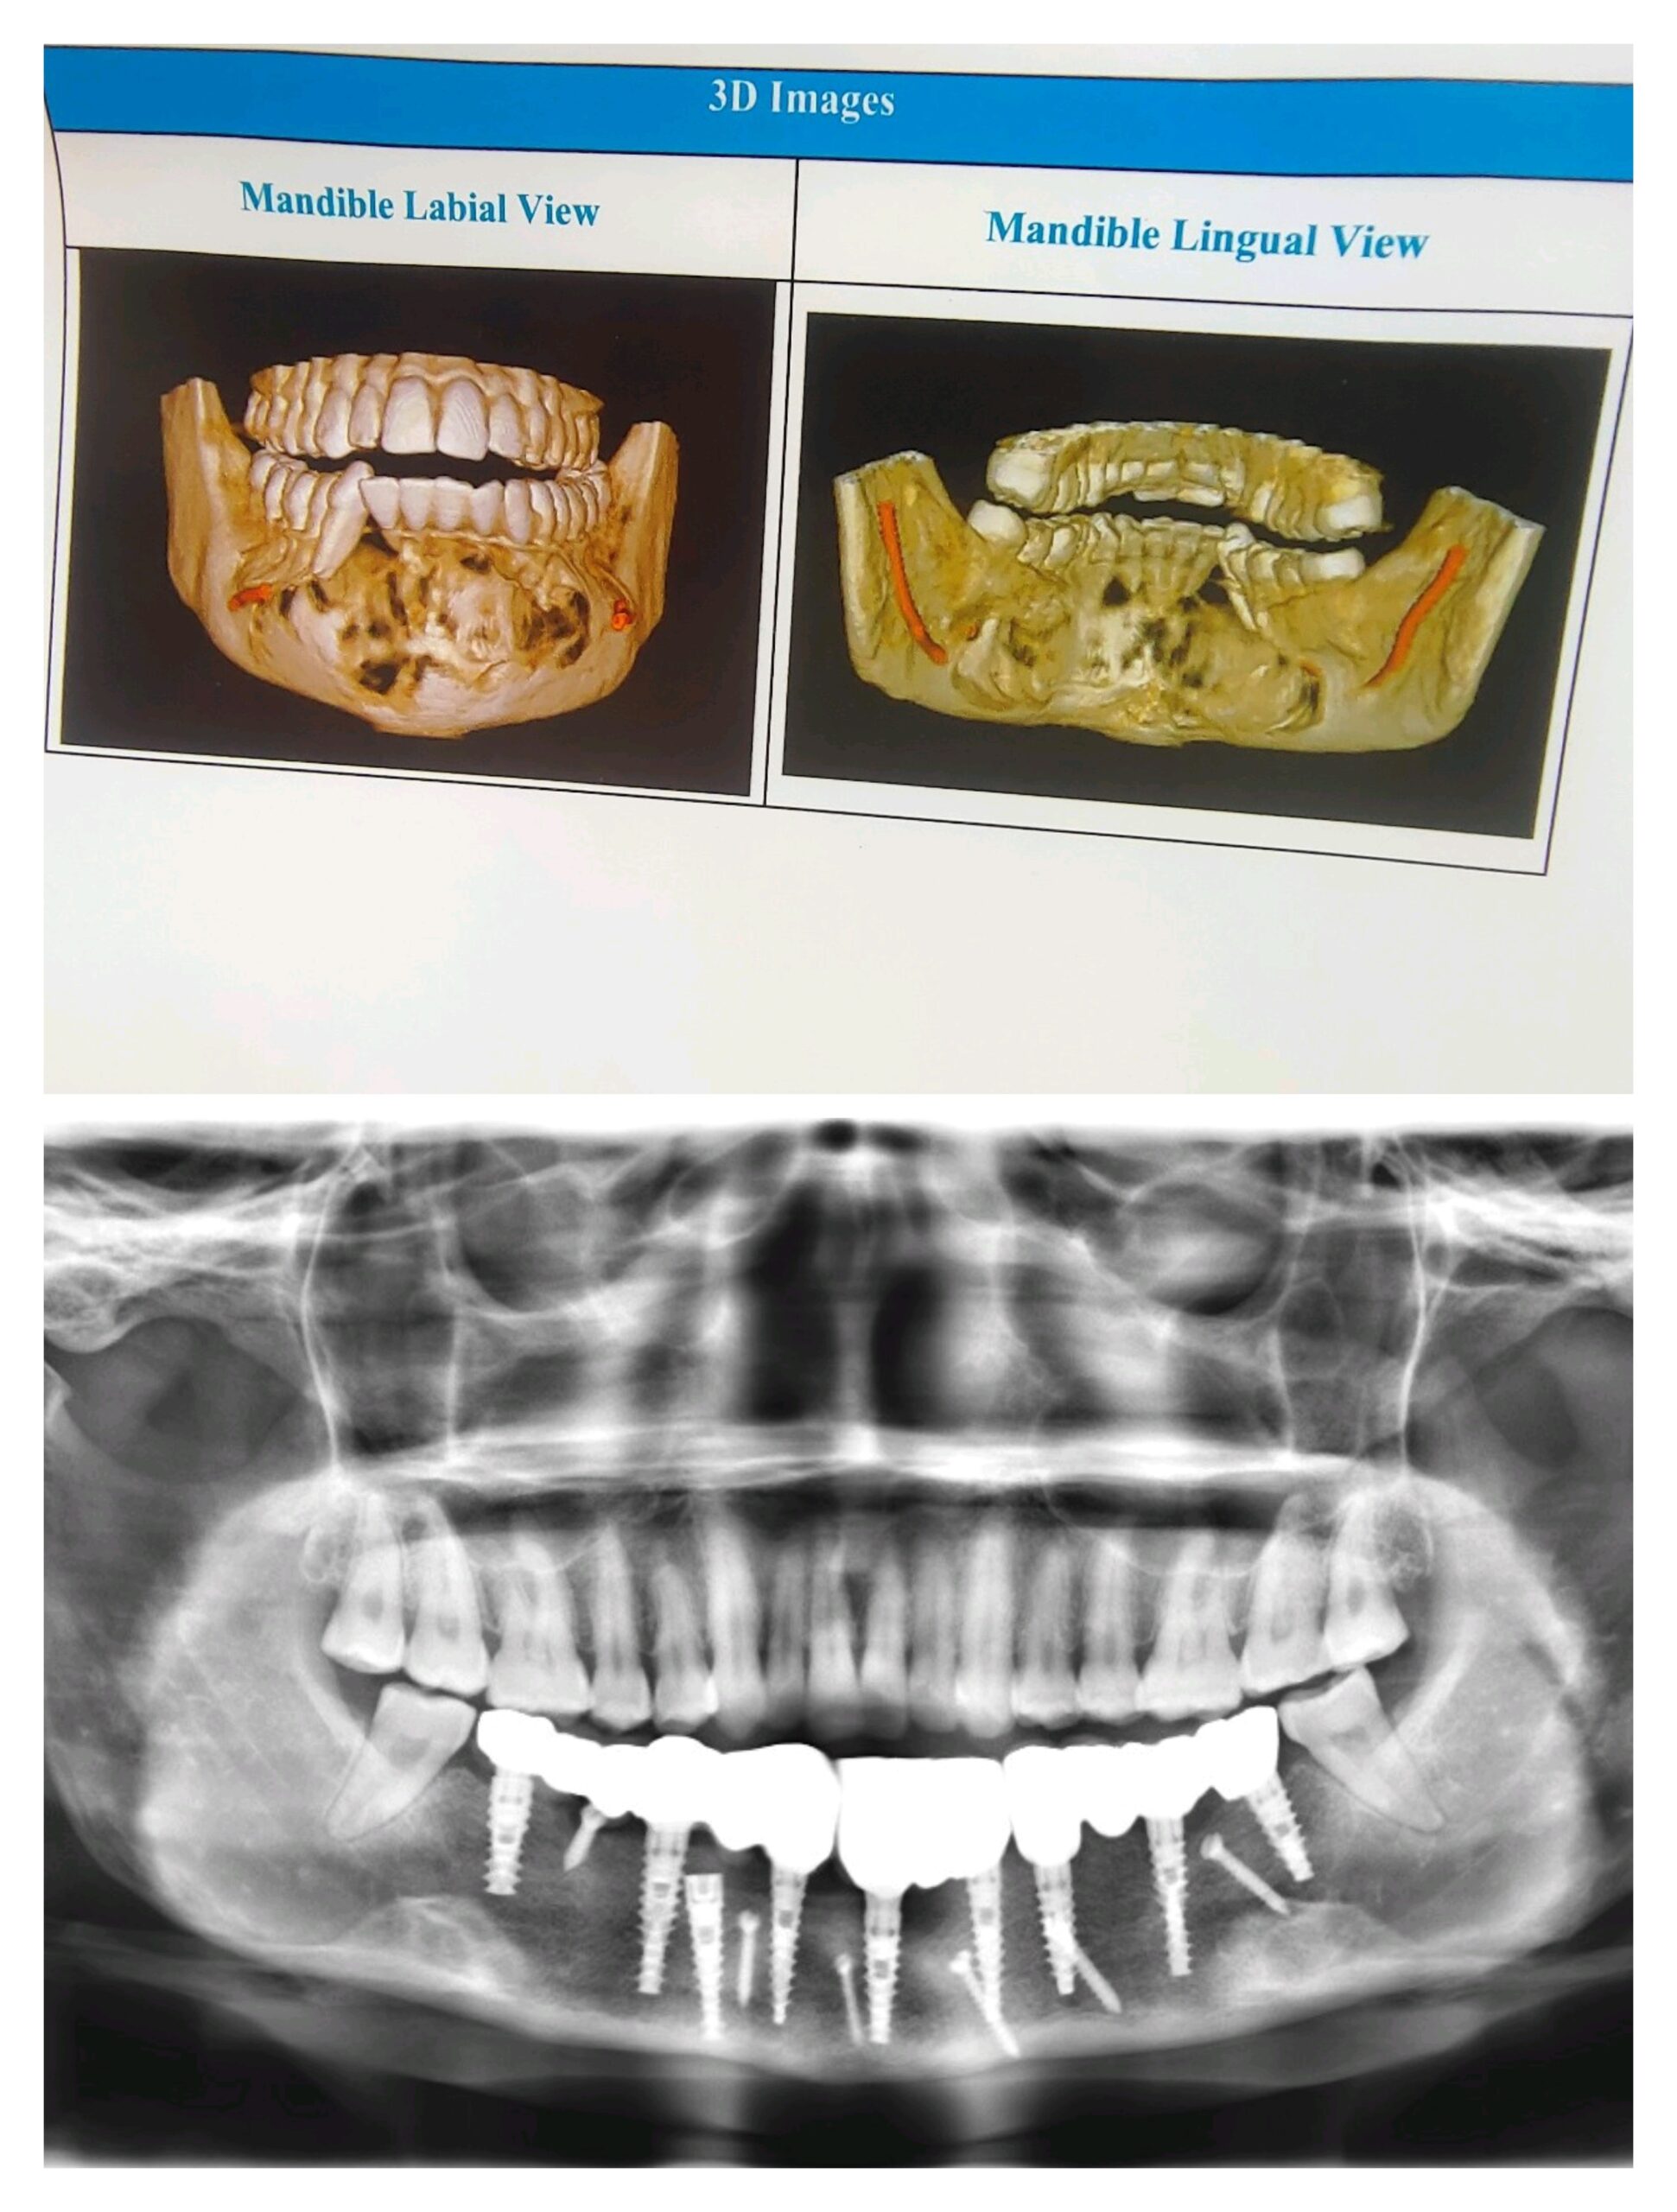

एम्स भोपाल के डेंटल विभाग ने एक बेहद दुर्लभ और जटिल सर्जरी को सफलतापूर्वक अंजाम दिया है। इस सर्जरी के तहत ट्यूमर के कारण काटना पड़ा निचला जबड़ा पैर की हड्डी से दोबारा बनाया गया और उसमें 13 दांत लगाए गए। यह उपलब्धि न केवल मरीज के जीवन में नई खुशियाँ लेकर आई है, बल्कि चिकित्सा जगत में भी एक बड़ी कामयाबी मानी जा रही है। 24 वर्षीय एक युवती मुंह में सूजन और बार-बार पस बनने की समस्या लेकर एम्स भोपाल आई थी। जांच में पता चला कि उसे बिनाइन ओडोन्टोजेनिक ट्यूमर नामक बीमारी है। गंभीर स्थिति को देखते हुए डॉ. अंशुल राय और उनकी टीम—डॉ. बाबूलाल, डॉ. ज़ेनिश, डॉ. सुदीप, डॉ. फरहान, डॉ. प्रधा और डॉ. दीपा—ने बहु-चरणीय सर्जरी करने का निर्णय लिया।

पहला चरण: पहले चरण में युवती के निचले जबड़े को काटकर ट्यूमर को पूरी तरह हटाया गया। ट्यूमर का आकार 12 सेंटीमीटर से अधिक था और उसके साथ 13 दांत भी निकालने पड़े। इस वजह से जबड़ा कमजोर हो गया और दांत भी नष्ट हो गए।

दूसरा चरण: जबड़ा और दांत निकल जाने के बाद युवती को भोजन करने में कठिनाई होने लगी, चेहरा विकृत हो गया और वह अवसाद से जूझने लगी। ऐसे में डॉ. अंशुल राय और उनकी टीम ने पैर की हड्डी (इलिएक क्रेस्ट) से नया जबड़ा बनाकर उसमें 9 डेंटल इम्प्लांट्स लगाए। इसके साथ ही, टीम ने मरीज को मानसिक रूप से मजबूत बनाने के लिए लगातार काउंसलिंग सेशन भी किए।

तीसरा चरण: लगभग 6 महीने बाद जब पैर की हड्डी निचले जबड़े से पूरी तरह जुड़ गई, तब तीसरे चरण में युवती के नए दांत लगाए गए। सर्जरी पूरी होने के बाद मरीज का चेहरा पहले जैसा हो गया, खाने-पीने की समस्या खत्म हो गई और उसका आत्मविश्वास लौट आया। अब वह सामान्य जीवन जी पा रही है और उसकी जीवन-गुणवत्ता पहले से कहीं बेहतर हो गई है।

डॉ. अंशुल राय, जो पिछले 20 वर्षों से डेंटल इम्प्लांट्स और सर्जरी कर रहे हैं, ने बताया कि मध्य भारत में पहली बार 12 सेंटीमीटर का जबड़ा पैर की हड्डी से बनाकर 13 दांत लगाने का यह सफल मामला सामने आया है। इस अनोखे केस को इंटरनेशनल इम्प्लांट्स जर्नल में प्रकाशन हेतु भेजा गया है। डॉ. राय ने कहा कि सबसे बड़ी सफलता यह रही कि लंबे समय से अवसाद में रह रही युवती फिर से सामान्य जीवन की ओर लौटी और उसके चेहरे पर मुस्कान लौट आई।